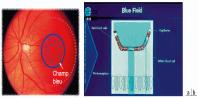

- eFig. 9-28 - Méthode entoptique du champ bleu